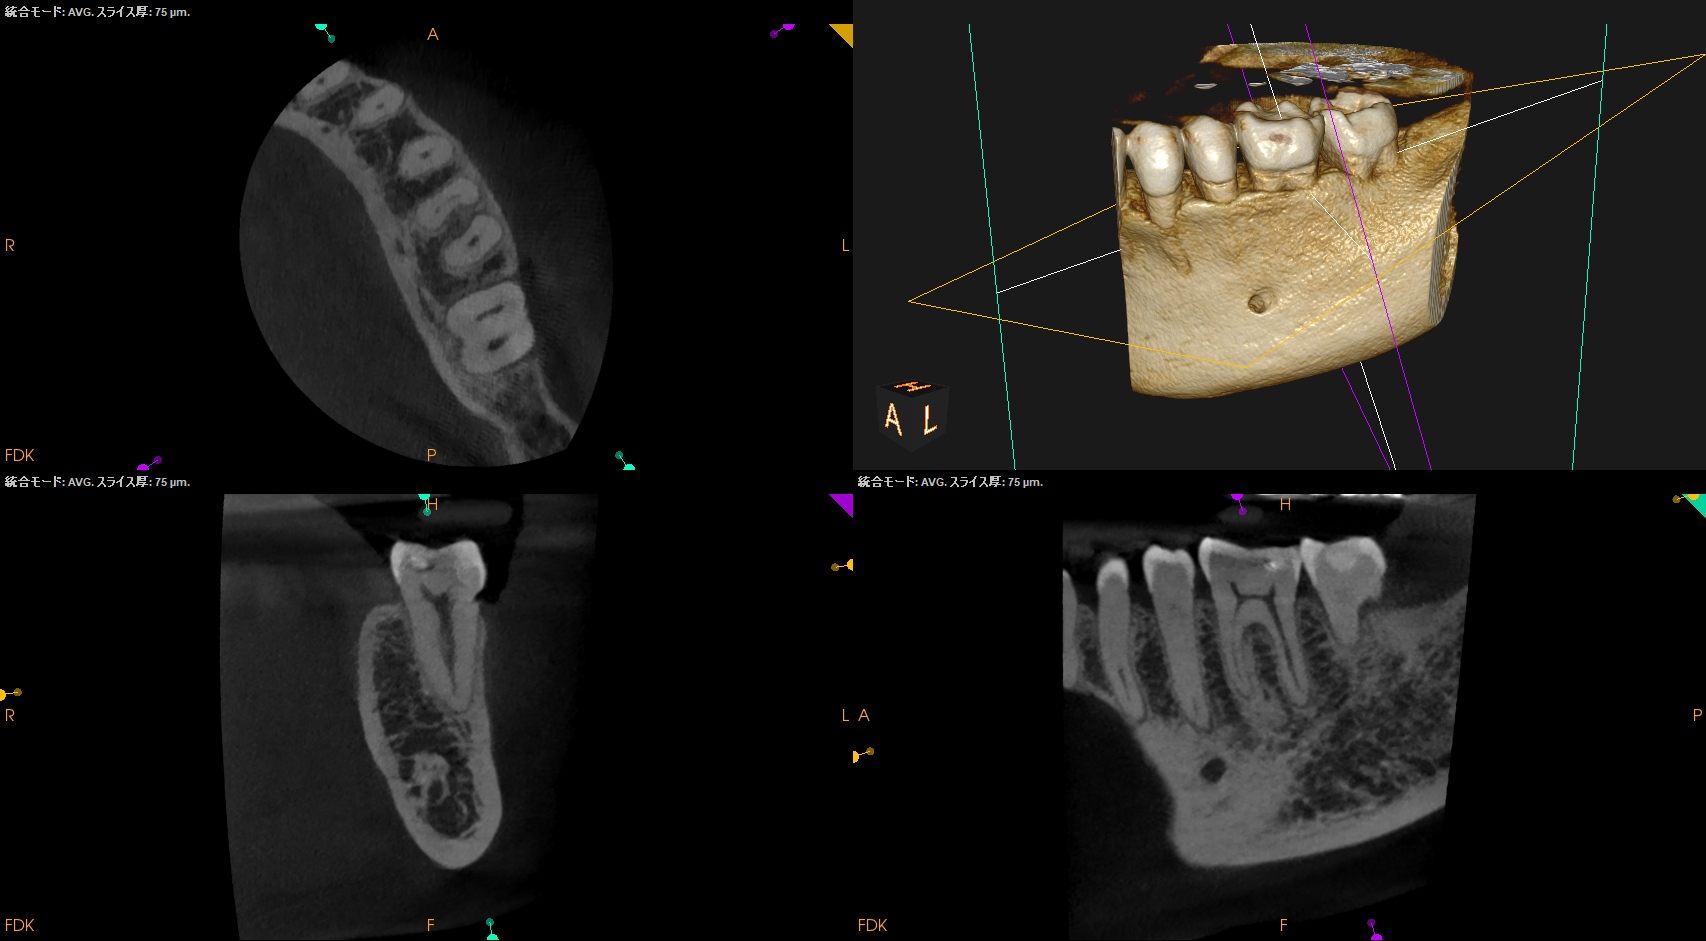

参考ケースは以下だ。

Dにはほぼ歯髄に修復物が覆いかかっている。

これは、

Asymptomatic irreversible pulpitisの可能性が高いだろう。

以下のように根管形成した。